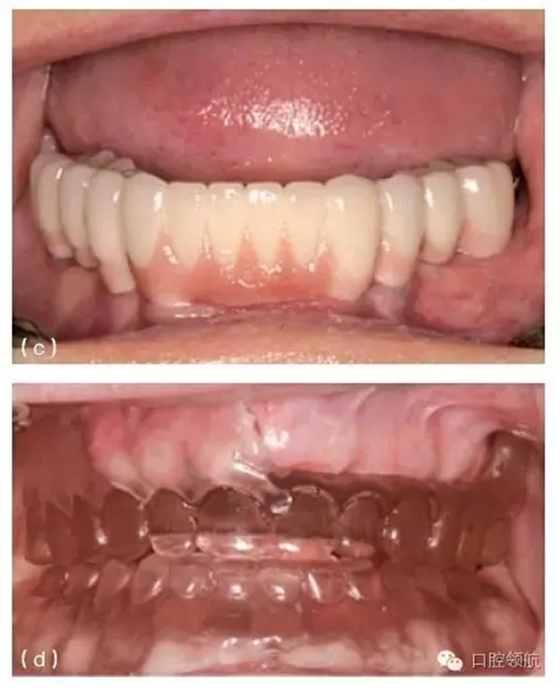

圖10.24 (a) 如圖所示上頜右側(cè)中切牙區(qū),種植體冠周圍的牙齦緣向根方移位。(b)金屬烤瓷冠頸部盡可能做得很薄,以試圖獲得一個(gè)較好的組織反應(yīng)。(c)如圖所示,種植體替代體上方的個(gè)性化基臺(tái)和金屬烤瓷冠。注意該冠較薄的金屬邊緣以及齦下部位沒(méi)有上瓷。(d)采用外科軟組織增量技術(shù)使該病例更美觀。(e)不良的種植體植入角度和切頸位置,會(huì)造成(a)圖中修復(fù)并發(fā)癥的發(fā)生。